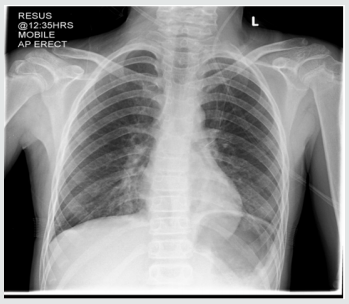

The rest of her systemic review was normal. She was able to eat and drink “normally” but bedside swallow was not formally assessed. She was treated for a respiratory tract infection with intravenous antibiotics and regular salbutamol nebulisers. A few hours later, she developed increased shortness of breath and a peri-arrest call was made. However, examination findings were unchanged, her management remained the same. Her bloods results were Hb 133, WBC 8.9, Plt 293, CRP 5, U&E NAD, LFT NAD. The CXR was reported as left lower lobe atelectasis with an increase of the peribronchial and perivascular interstitial infiltrates (Figure 1). she was reviewed by a second Paediatric Consultant in the ward later, who felt this was more likely to be an upper airway obstruction. He stopped the salbutamol nebulisers, continued the Atrovent nebulisers, started prednisolone and advised to suction intermittently, request an ENT review and arrange a neck X-ray and barium swallow. Neck X-ray was normal (Figure 1). An ENT Consultant reviewed the following day with flexible nasendoscopy which revealed a normal larynx, good vocal cord movement and very slight inflammation on the right arytenoid. The nasendoscopy findings were noted to be insufficient to explain the symptoms. The ENT impression was laryngopharyngeal reflux. She was put on Gaviscon Advance after food and before bedtime. she gradually improved over next three days. She was discharged home on Gaviscon Advance. Barium swallow, done a month later, was reported ‘the mid and distal oesophagus giving a shaggy appearance most likely due to Oesophageal Candidiasis’ (Figure 2).